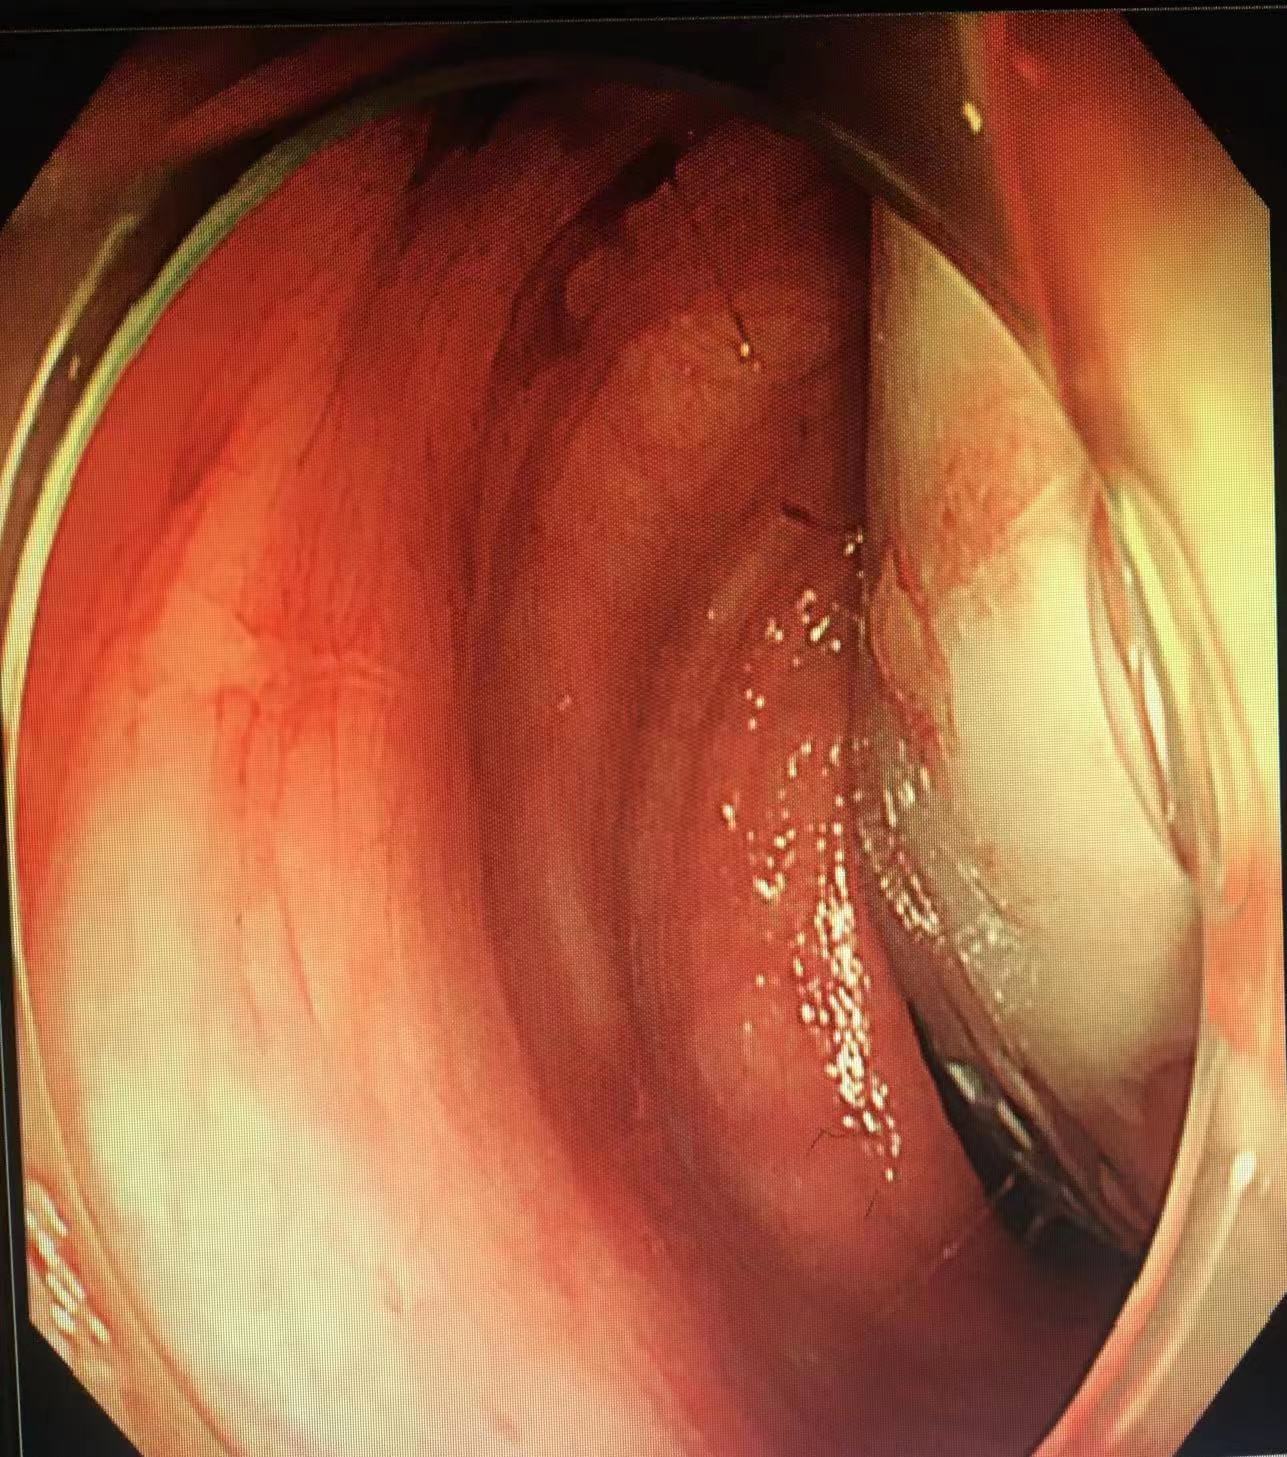

手术开始,通过肠镜观察到,一管状异物被紧紧地嵌顿在患者直肠乙状转弯处。由于患者曾多次尝试自行取出异物,导致直肠高度水肿,犹如一个橡皮套将异物包裹得十分紧实,还伴有溃疡出血,异物的一头仅隐约可见,很难找到有效的着力点移动异物,内镜下操作困难重重。

吕培华医生尝试使用圈套器、异物钳、鳄嘴钳等多种器械设备,反复不断地调整着角度、方向,在狭小的肠道空间中艰难地让异物沿着生理曲度挪移。每一分每一秒,都透着紧张与专注。在她的全神贯注与不懈努力下,异物一点点往肛门口移动。